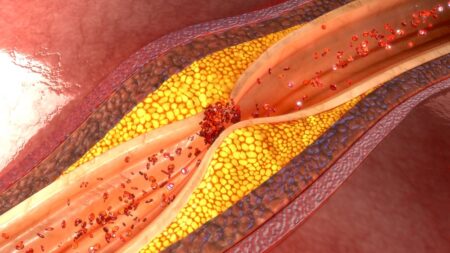

Prevenci a léčbu ucpaných cév výrazně ovlivňuje váš jídelníček. Odborníci radí zařadit tyto potraviny